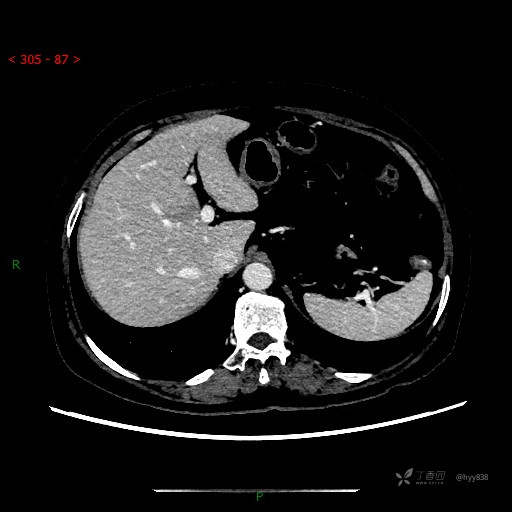

增强动脉期